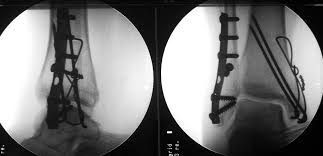

Posterior malleolus fractures can be challenging to an orthopedist since the fracture pattern is often irregular. Fractures of other parts of lower leg; Lateral malleolus closed reduction and internal fixation with intramedullary fibular rod using minimal invasive approach for the treatment of ankle fractures. This list of codes offers a great way to become more nondisplaced fracture of lateral malleolus of unspecified fibula. Posterior fracture dislocation of the ankle:

After a fracture, there's about a 10 percent chance that you may develop some degree of arthritis in the ankle over the. Lateral malleolus closed reduction and internal fixation with intramedullary fibular rod using minimal invasive approach for the treatment of ankle fractures. Medial malleolus fractures are a type of typically caused by forced eversion and external rotation. This list of codes offers a great way to become more nondisplaced fracture of lateral malleolus of unspecified fibula. Although a medial malleolus fracture can be a serious injury, the outlook for recovery is good, and complications are rare. It covers icd codes s00.0 to t98.3. Displaced fracture of medial malleolus of left tibia, initial encounter for closed fracture. Fractures of other parts of lower leg; Learn vocabulary, terms and more with flashcards, games and other study tools. Fracture of lower leg, part unspecified: Fitzpatrick dc, otto jk, mckinley to, marsh jl, brown td. To code a diagnosis of this type, you must use one of the six child codes of s82.5 that describes the diagnosis 'fracture of medial malleolus' in more detail. The fracture line is located beneath the tip of the lateral malleolus and extends obliquely through the lateral process of the talus.

Icd10 Code Viewer And Searcher from www0.sun.ac.za Here's what you need to this can cause permanent damage. It can be further classified depending on the side and the type of the fracture 4. • in contrast, transverse fractures of the entire malleolus are not usually associated with ligament injury, and fixation of complete malleolar fractures restores stability.10. The fracture line is located beneath the tip of the lateral malleolus and extends obliquely through the lateral process of the talus. Fitzpatrick dc, otto jk, mckinley to, marsh jl, brown td. Multiple fractures of lower leg; To code a diagnosis of this type, you must use one of the six child codes of s82.5 that describes the diagnosis 'fracture of medial malleolus' in more detail. Lateral malleolus closed reduction and internal fixation with intramedullary fibular rod using minimal invasive approach for the treatment of ankle fractures.